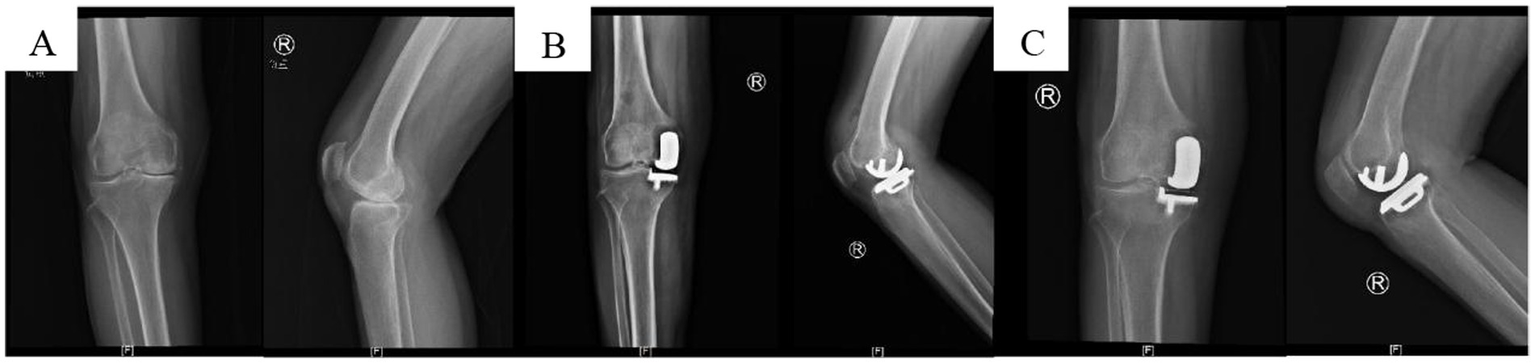

Figure 2

Schematic diagram of incision suture methods. (A) Continuous intradermal suture; (B) traditional intermittent suture.

X-ray images of anterior medial knee OA before and after UKA surgery. (A) Preoperative image; (B) postoperative 2-day image; (C) postoperative 3-month image.